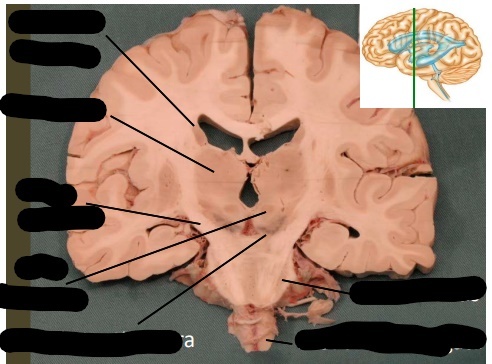

lable, note important features

uncus is seen on the ventral (inferior) surface of cerebram, pointing towards the mamillary bodies or optic chiasm. following the uncus, the change in the basic organization of cortex indicates the hippocampus